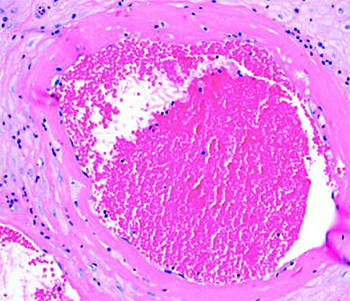

Тромбоз межворсинчатого пространства (см. рис. 4). В сосудах формируются слоистые тромбы, оттесняя на периферию ворсины, которые перестают участвовать в газообмене.

Иван Сахаров обратил внимание, что изменения настолько яркие, что видны на макроскопическом уровне. Если в норме плацентарная ткань рыхлая, насыщенного красного цвета и напоминает пропитанную кровью губку, то при тромбозе становится желтовато-серой, очень плотной и сухой. В ней имеются заполненные кровью участки — это кровоизлияния и формирующиеся тромбы.